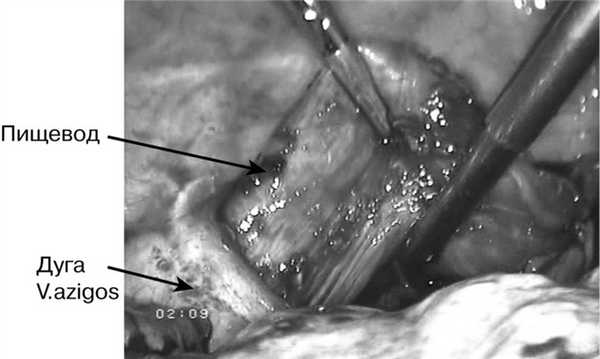

Предпочтение отдавали выполнению эзофагопластики целым желудком (39 человек). Первоначально формирование трансплантата производилось из лапаротомного доступа (45 больных). В последующем нами была разработана техника трансторакальной экстирпации пищевода из правостороннего доступа с одномоментной видеолапароскопической гастропластикой (11 человек). Учитывая трудности при выделении пищевода из рубцовых сращений и опасность повреждения прилежащих органов, производилось пересечение пищевода над дугой непарной вены с мобилизацией проксимального конца до верхней апертуры грудной клетки, а дистального - до диафрагмы (рис. 1).

Рис. 1. Выделение пищевода над дугой непарной вены.

Предпочтение отдавали эзофагопластике целым желудком (n=39). Первоначально трансплантат формировали, используя лапаротомный доступ (n=45). В последующем нами была разработана техника трансторакальной экстирпации пищевода из правостороннего доступа с одномоментной видеолапароскопической гастропластикой (n=11). Учитывая трудности при выделении пищевода из рубцовых сращений и опасность повреждения прилежащих органов, его пересекали над дугой непарной вены с мобилизацией проксимального конца до верхней апертуры грудной клетки, а дистального - до диафрагмы (рис. 1).

Рис. 1. Интраоперационная фотография. Выделение пищевода над дугой непарной вены.